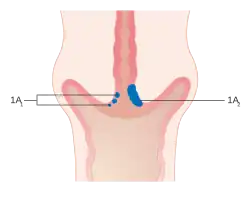

The location of cervical cancer can be described in terms of quadrants, or corresponding to a clock face when the subject is in supine position.

The location of cervical cancer can be described in terms of quadrants, or corresponding to a clock face when the subject is in supine position.

-

Stage 1A cervical cancer